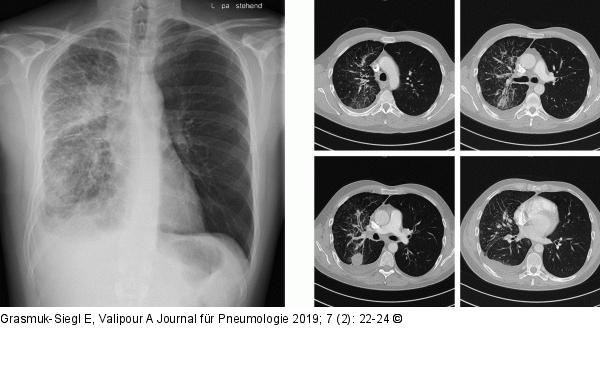

Abbildung 2: Radiologie